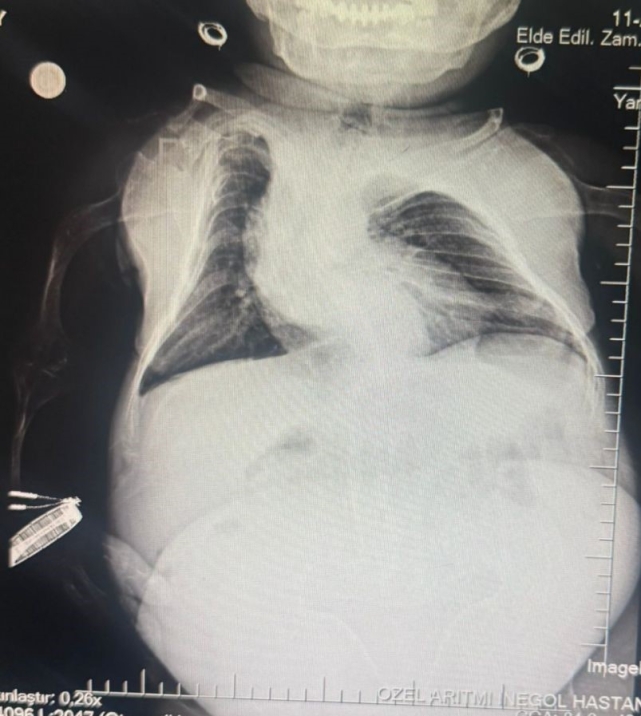

Halk arasında cücelik olarak bilinen Akondroplazi rahatsızlığı ile dünyaya gelen 30 yaşındaki Nurdan Tüfekçi, son 1 yıldır yaşadığı karın ağrısı şikayeti nedeniyle birçok hastaneye başvurarak tedavi gördü. Son olarak İnegöl'deki özel bir hastanenin kadın hastalıkları bölümüne başvuran 80 santim uzunluğunda ve 24 kilogram ağırlığındaki Nurdan Tüfekçi'nin yapılan tetkiklerinde yumurtalığında 3 kilogram kist olduğu tespit edildi.

Anestezi Doktoru Mahmut Gül, "Hastamız 30 yaşında. 80 santimetre boyunda, 24 kilo ağırlığında bir kardeşimiz. Kendisinin yumurtalıklarında kist olduğu için ameliyat olması gerekti. Biz bu ameliyatta hastamıza önce büyük bir damar yolu açtık kasıktan. Çünkü damar yolunun çok önemi var ve daha sonrasında ameliyat sırasında belinden uyuşturduk ve ameliyatı sorunsuz bir şekilde belden uyuşturmayla hastamız uyanık bir şekilde tamamladık. Hastadan 3 kilo kist çıktı. Öncesinde 24 kilo olan hastamız, ameliyat sonrasında 21 kiloyla şifalı bir şekilde serviste yatıyor. Ameliyatı bugün oldu. Şu anda da serviste hastamız. Bu tür ameliyatlarda uyutmak hastamız açısından oldukça risklidir. Biz o yüzden bölgesel anesteziyi yani belden uyuşturmayı tercih ettik. Literatürde çok olmayan bir hasta ve güvenli bir şekilde hastanemizde bu ameliyat tamamlandı" dedi.

Kadın Hastalıkları Uzmanı Mustafa Kır, "Hastamızda 20 santimlik tümör vardı kistlik yapıda. Onu başarılı bir operasyonla çıkarttık" şeklinde konuştu.